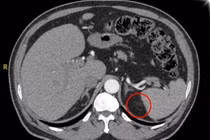

Ảnh minh họa/ Nguồn internet